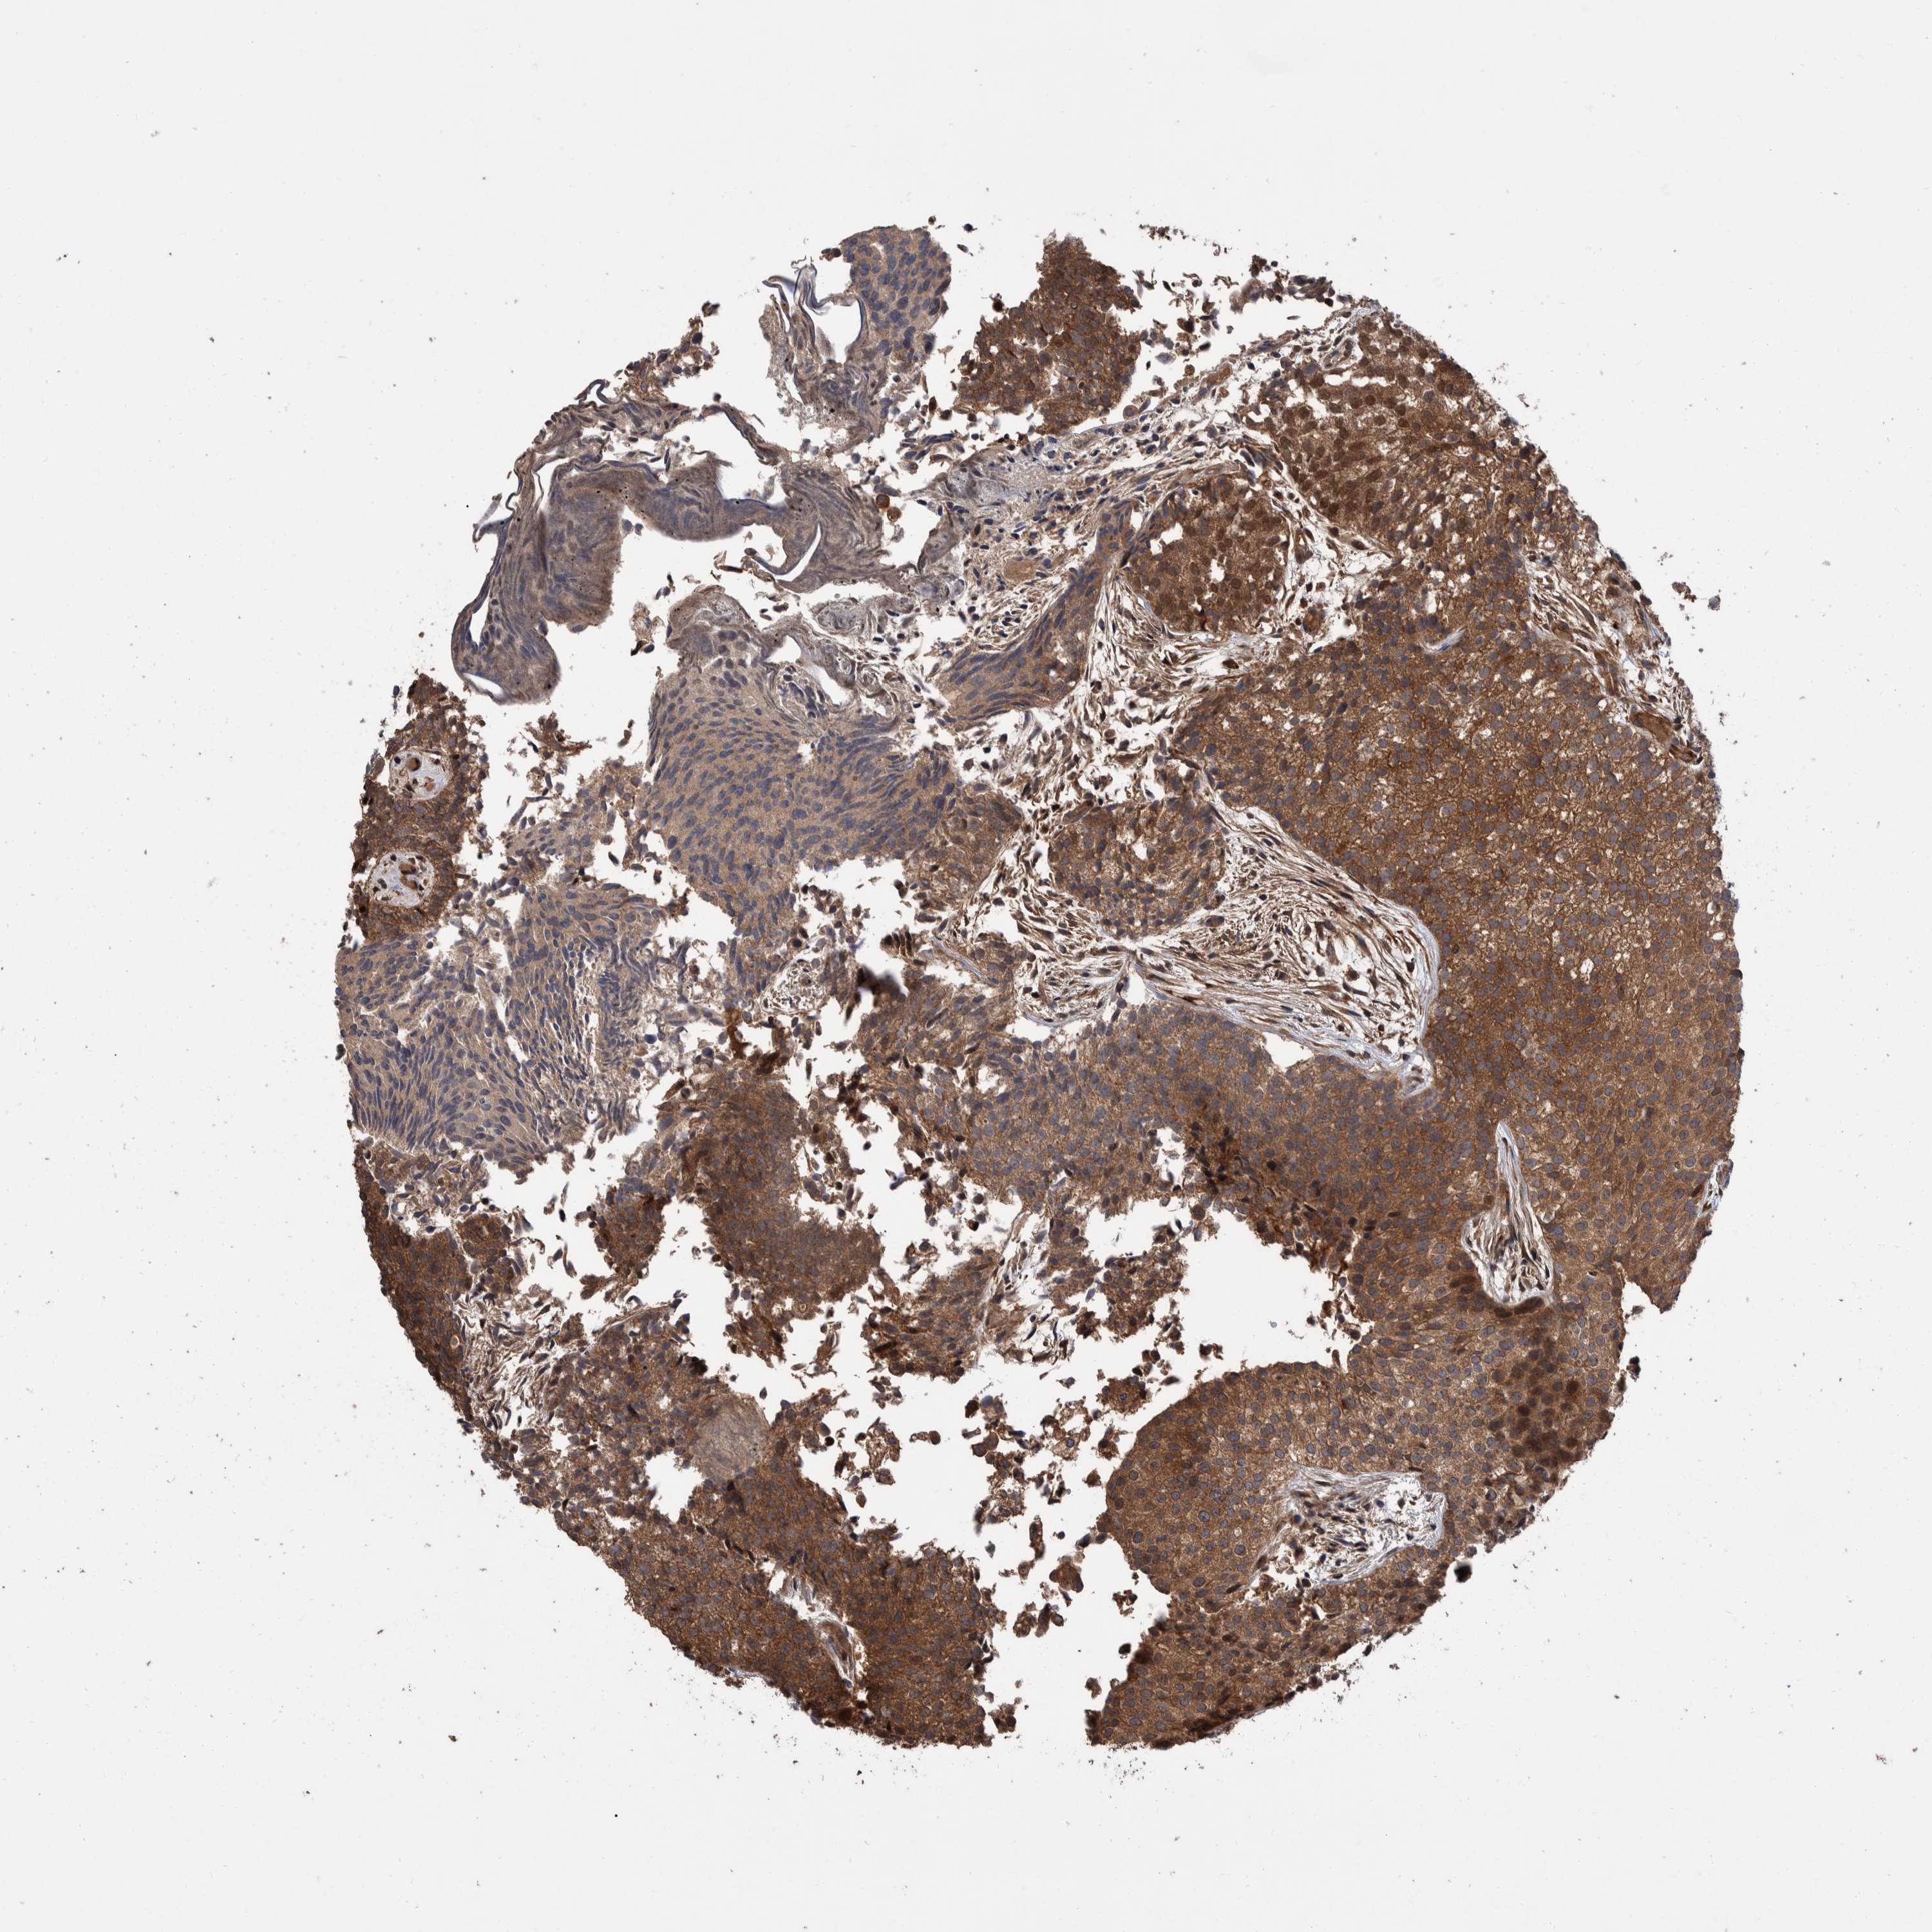

UROTHELIAL CANCER - Protein expressioni

A mouse-over function shows sample information and annotation data. Click on an image to view it in a full screen mode. Samples can be filtered based on level of antibody staining by selecting one or several of the following categories: high, medium, low and not detected. The assay and annotation is described here.

Note that samples used for immunohistochemistry by the Human Protein Atlas do not correspond to samples in the TCGA dataset.

Antibody stainingi

Antibody staining in the annotated cell types in the current human tissue is reported as not detected, low, medium, or high, based on conventional immunohistochemistry profiling in selected tissues. This score is based on the combination of the staining intensity and fraction of stained cells.

Each image is clickable and will lead to virtual microscopy that enables deeper exploration of all samples and also displays staining intensity scores, fraction scores and subcellular localization as well as patient and tissue information for each sample.

Antibody HPA023230

Antibody CAB006260

Urothelial carcinoma, Low grade

Urothelial carcinoma, High grade